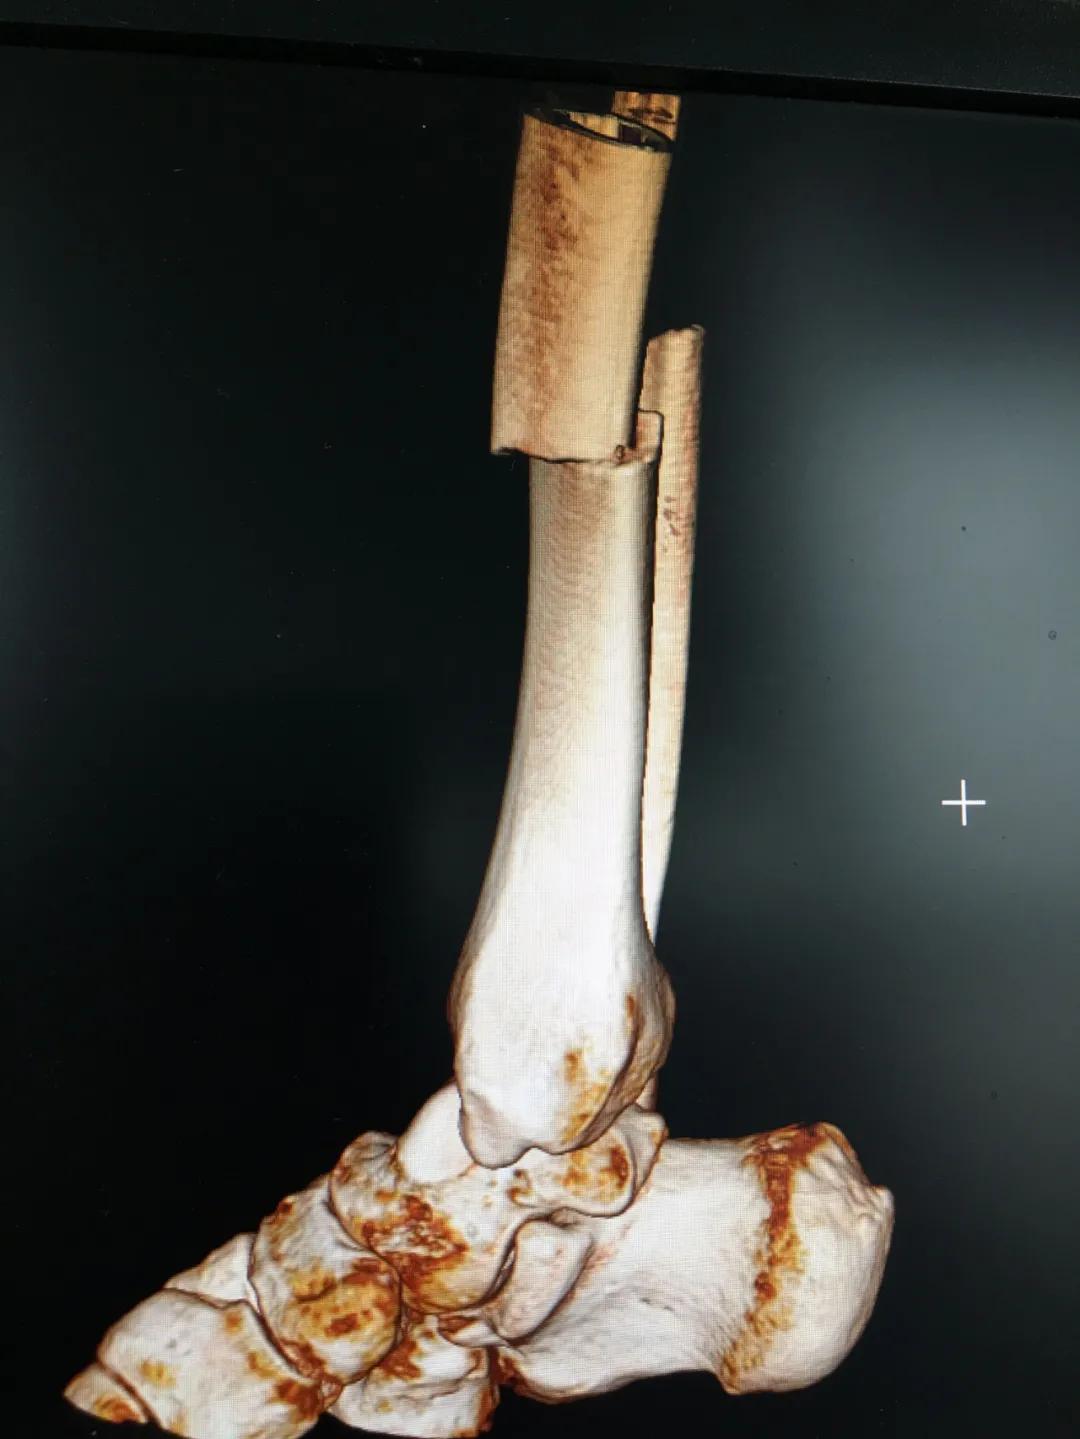

刘阿姨半个月前骑电动车时与小轿车相撞,导致了左胫腓骨粉碎性骨折,小腿骨碎成了三段。"然而,在术前丈夫周先生对刘阿姨的治疗却拿不定主意。“我妻子身上有多种基础疾病,患高血压15年,糖尿病也有8年多了。这里的诊疗技术,能不能保障手术的安全?手术前,我们家属的心中确实也很忐忑!"由于对我院创伤技术水平不太了解,周先生已经准备要转院治疗。

为患者实施的骨折微创复位固定技术是创伤骨科的特色技术。相较传统手术需要20公分的切口,微创手术只需要3公分左右。闭合复位髓内钉固定技术、经皮插板内固定技术(mippo技术)、闭合复位空心螺钉固定技术等一系列的微创复位固定技术,具有切口小、出血少、创伤小、愈合快、疤痕小等优点,骨折术后并发症明显降低,患者还可以早期负重功能锻炼。

另一位患者朱先生因车祸导致了右胫腓骨骨折,同样的小腿三段骨折,实施了微创闭合复位髓内钉固定术后,目前已经逐步进行康复功能锻炼。